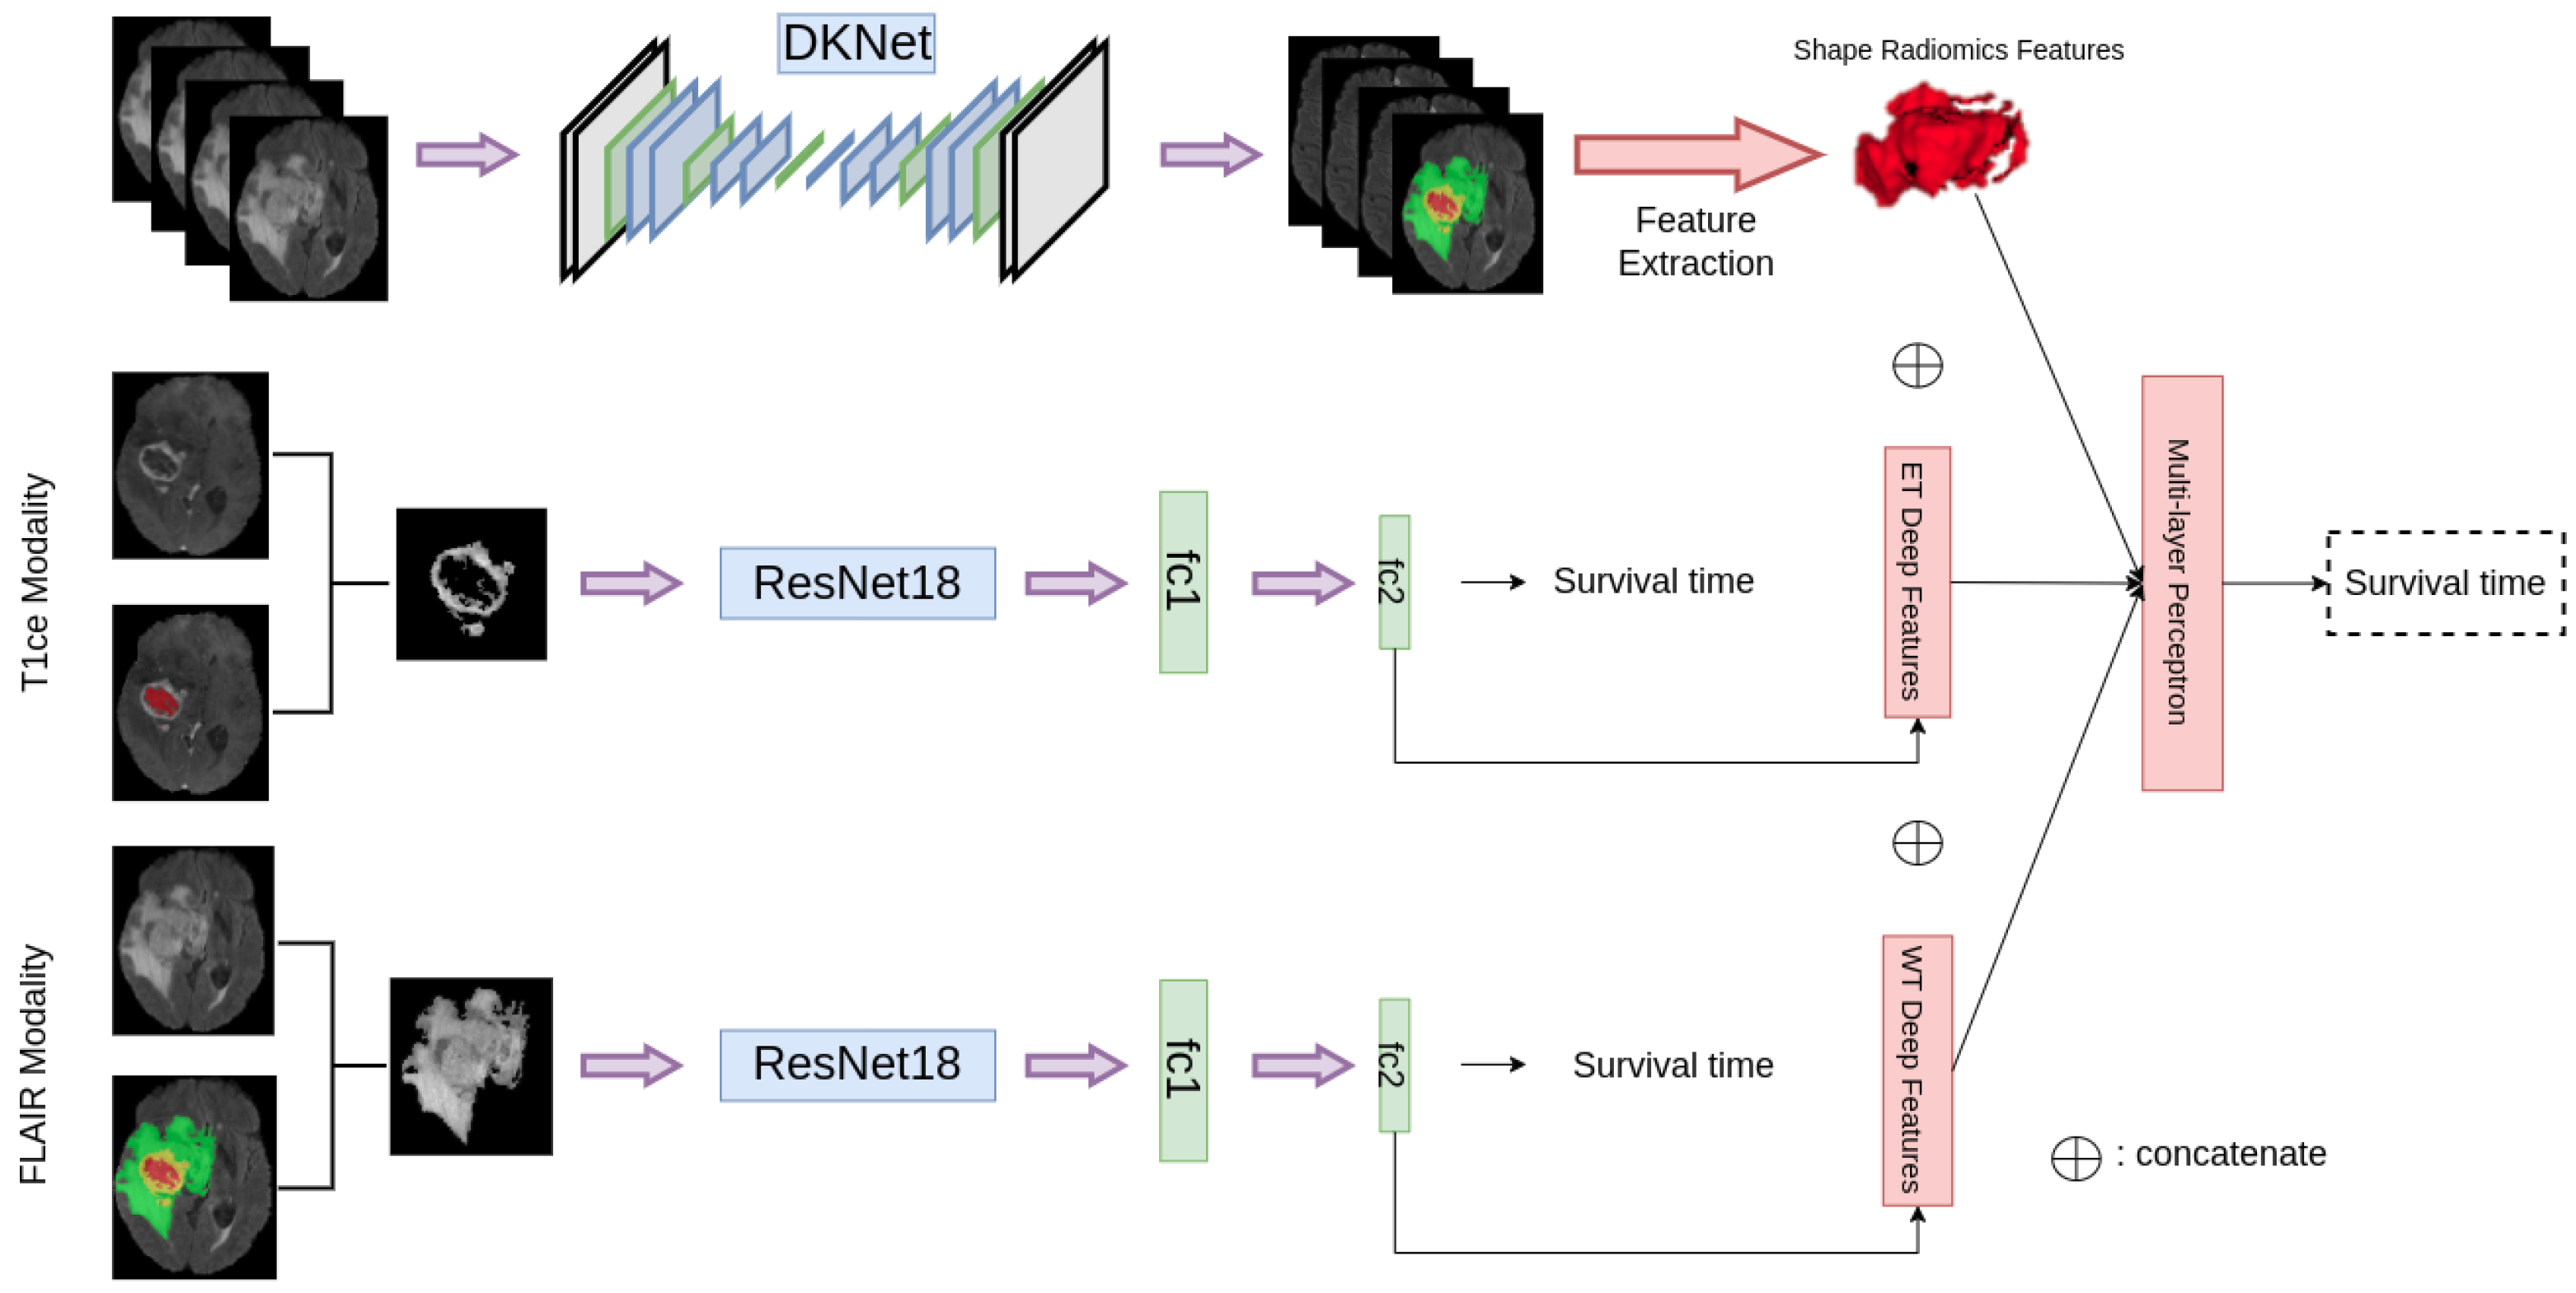

3.5. Deep Feature Extraction

3.6. Overall Survival Prediction